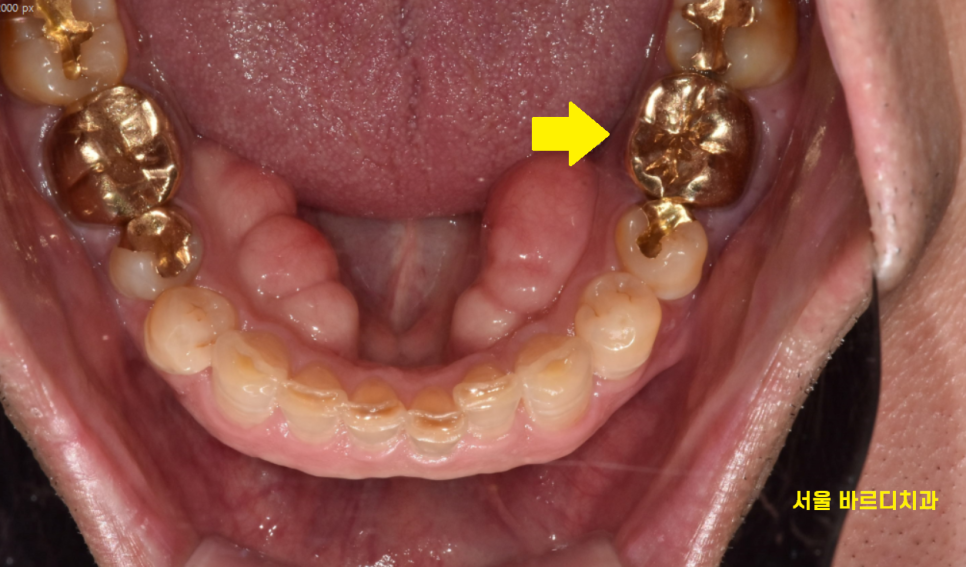

3년만에 치과를 방문해주신 환자분 사진입니다.

그동안은 바쁘기도 하고

불편한게 없어서 안오셨다고 하네요.

최근에 아몬드를 씹고 나서

치아가 계속 아프다고 하셨는데요.

큰 사진에서도 문제가 많아보였습니다.

딱봐도 이상해보이는 치아를

정밀하게 검사해보니

치아뿌리 파절, 부러짐이 확인되었습니다.

그 상태에서 자꾸 씹다보니

뿌리 주변 뼈가 녹아서

까맣게 보이네요~